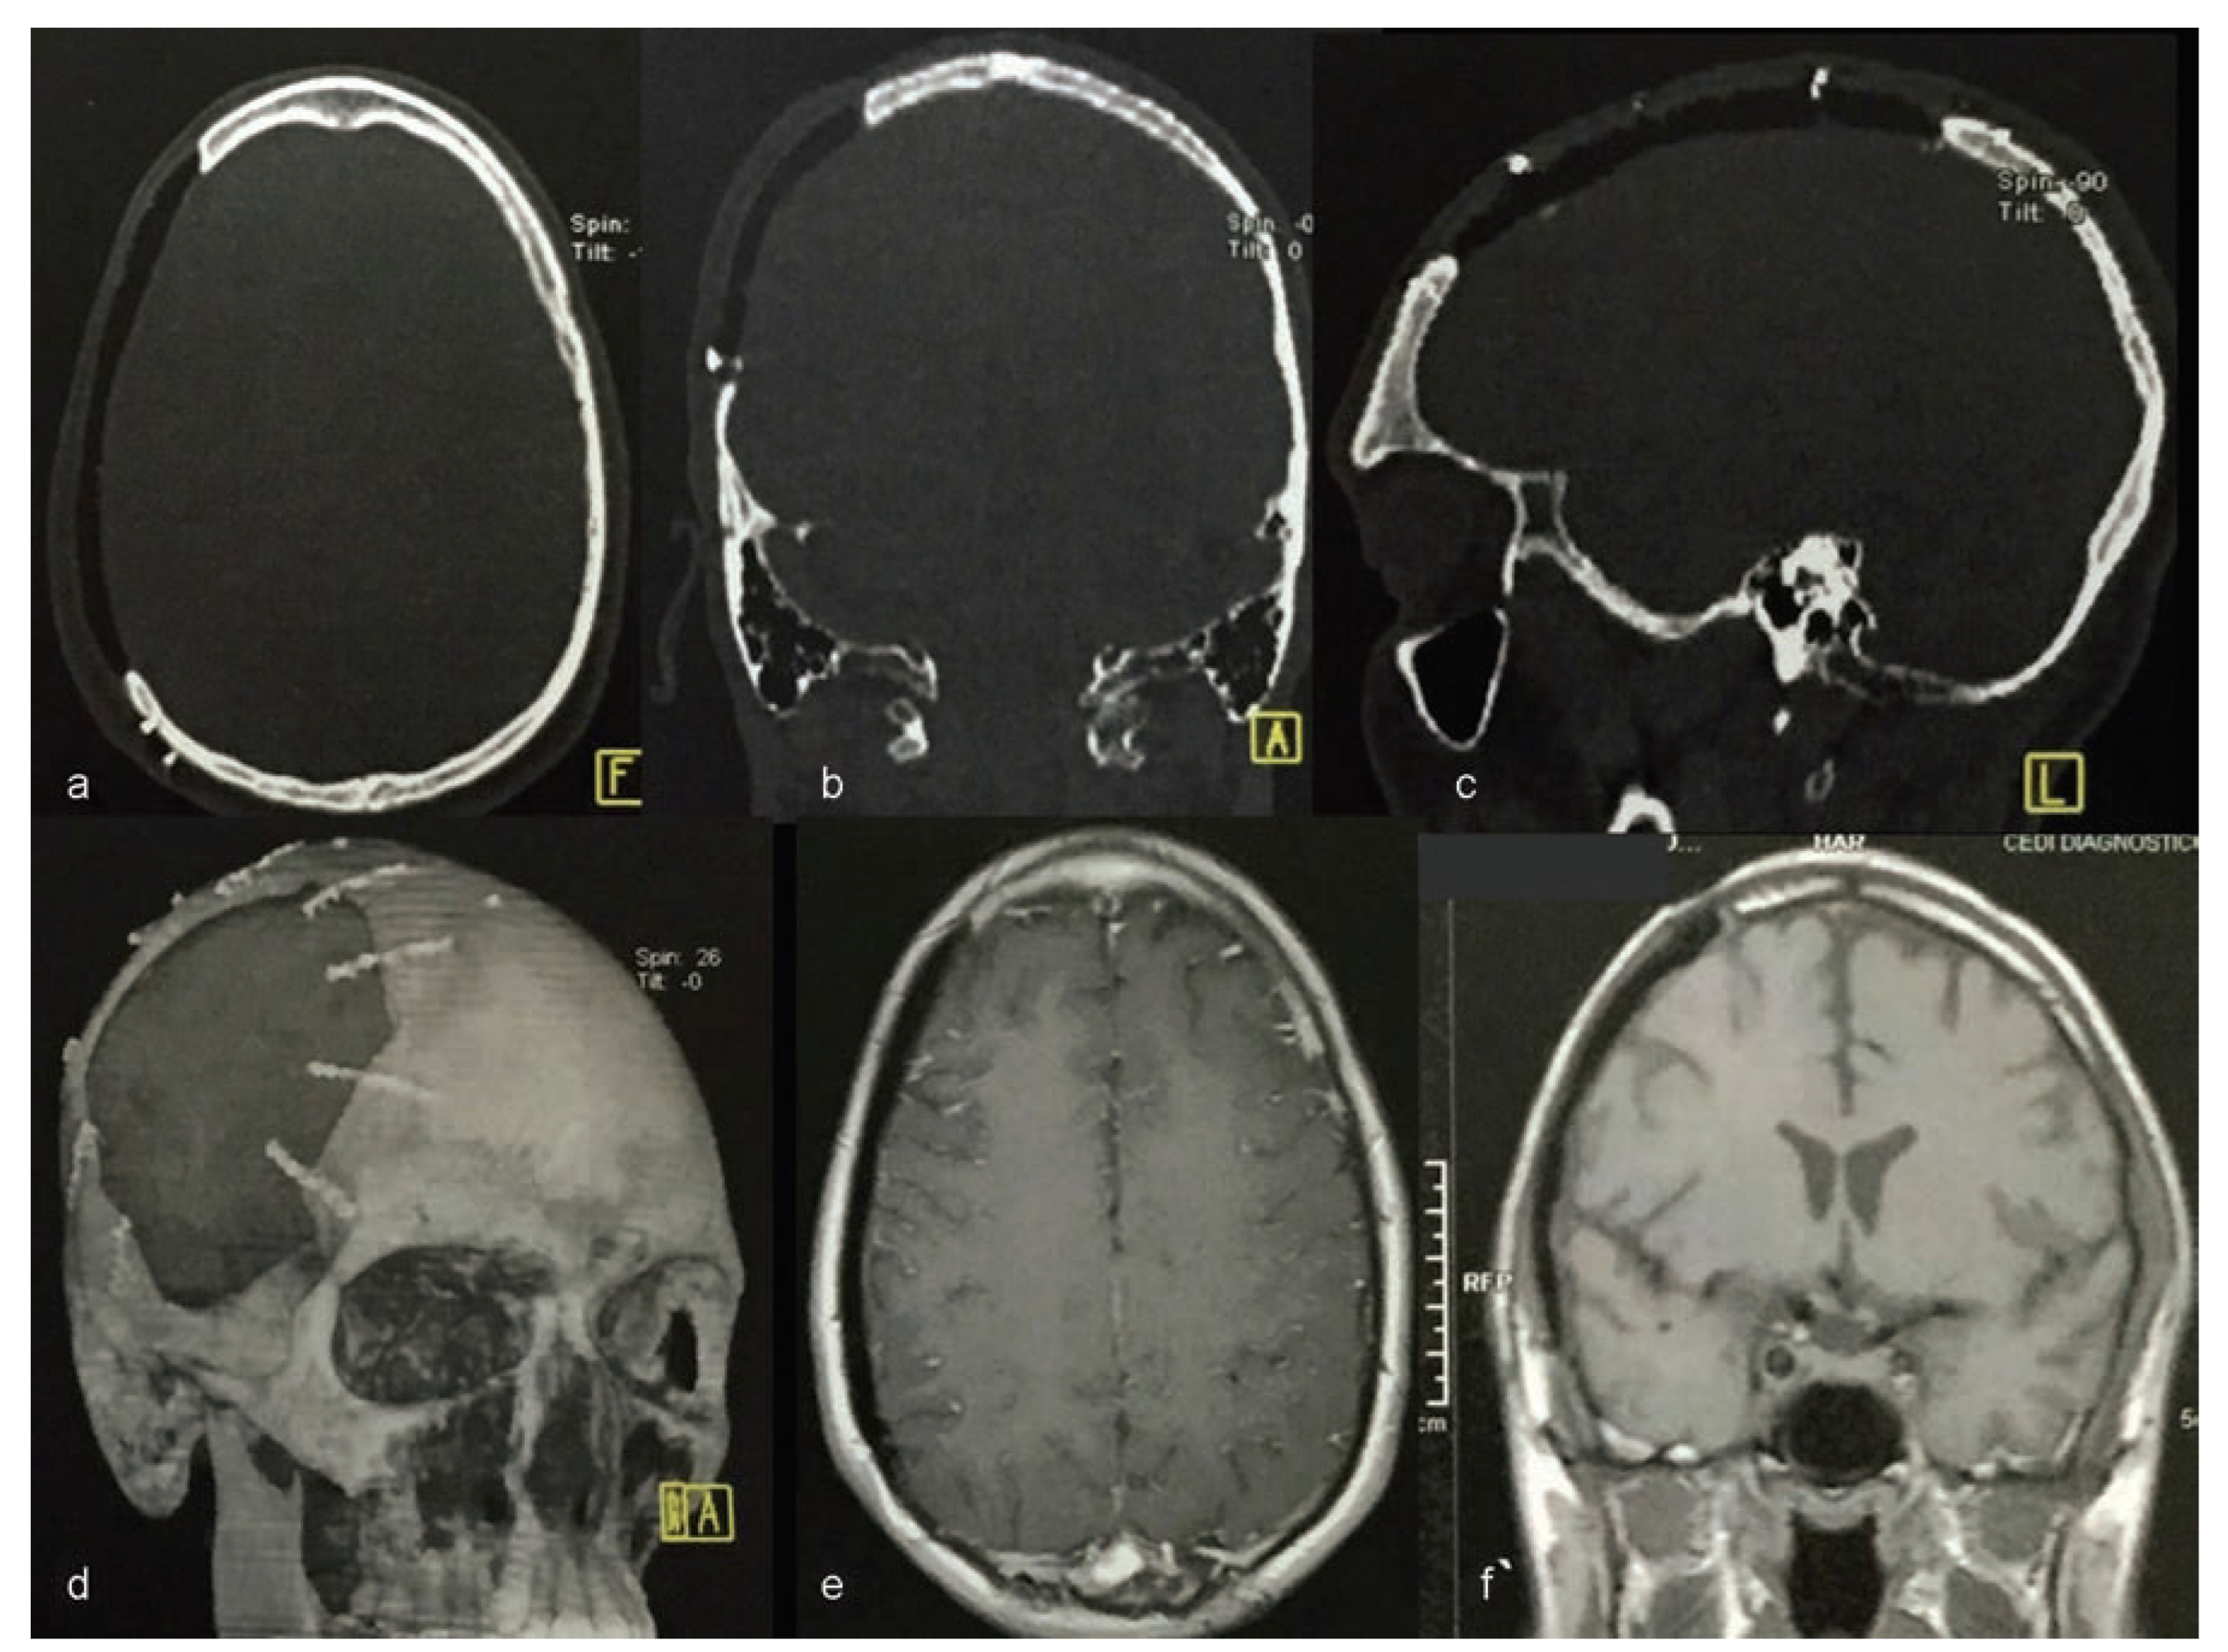

Computerized tomography (CT) was conducted using a 4-channel helical CT scanner Medical Toshiba Asteion 4-slice CT Scanner (Toshiba America Medical Systems, Inc., Tustin, CA). Axial, coronal, and sagittal sections and three-dimensional (3D) reconstruction were conducted (Figure 3).

The CT scan enabled the construction of the prototype prosthesis using the castor bean polymer. This was done to protect the brain and to rebuild the general anatomical contours of the skull.

Figure 11. Postoperative computed tomography (ad) and magnetic resonance imaging (e,f) view. No inflammatory features.